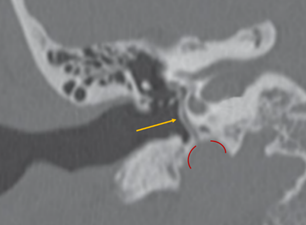

Arteria estapedial persistente

Figura 10. Arteria estapedial pesistente |

La arteria estapedial persistente (ASP) es un vaso pequeño anormal que surge de la porción petrosa de la arteria carótida interna y atraviesa el oído medio. Es el resultado de la falla de la regresión de la arteria estapedial embrionaria. La prevalencia varía entre el 0,02 y el 0,48% en la población general (Fig. 10-12).

El hallazgo incidental durante la cirugía puede resultar en hemorragias si no se identifica y maneja adecuadamente. Además, este hallazgo puede ser motivo para interrumpir el procedimiento quirúrgico.

|

Figura 11. Arteria estapedial (flecha amarilla) y porción petrosa de carótida (líneas rojas) |